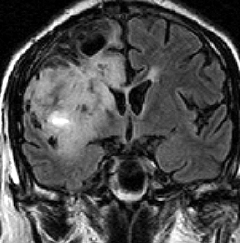

症候性てんかんのみで発症した右側頭葉と島回のグレード2オリゴです。左のT2,中央のフレアではグレード2びまん性星細胞腫と鑑別はできません。認知機能などは正常でした。

何と言っても診断的価値があるのは 石灰化 carcification です。左のCTの中央にみえる白い部分が石灰化です。この程度の石灰化でも診断的な価値があります。1p/19q codeletionがあるオリゴでした。病理では,均一な小型の円形核を有する細胞と多数の毛細血管 chickin-wire network がみられます。部分摘出後,放射線治療とテモゾロマイド化学療法でコントロールできています。